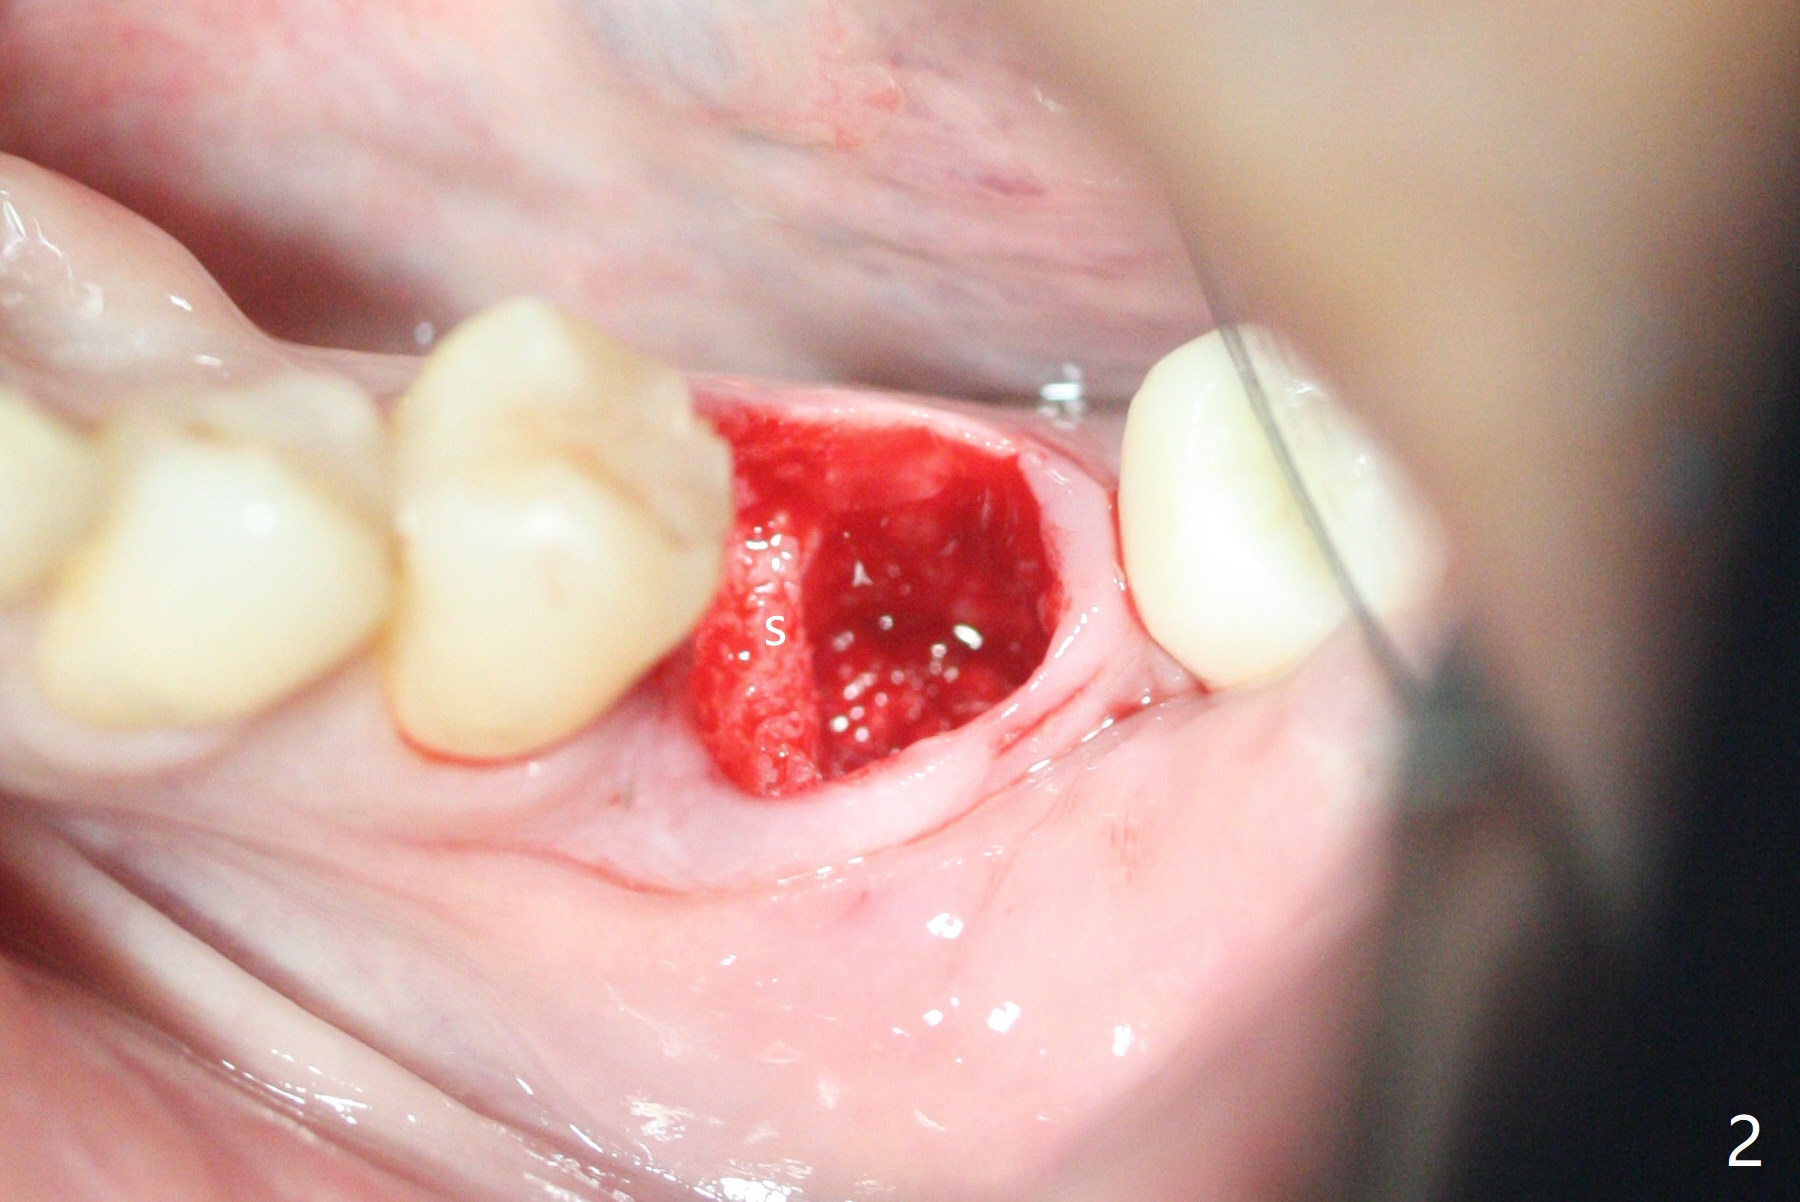

Venopuncture is conducted (Fig.1) for PRF and sticky bone (cortical chip and .5 cc ß-TCP). After use of proximators at #19, cowhorn forceps are applied, resulting in metal crown dislodgement. Since there is distal bone loss, distal socket sheath is contemplated. The tooth is sectioned. When an elevator is inserted between the roots, the distal root is loosened first. The 2 roots are removed, revealing a rounded end septum (Fig.2 S) and a larger distal socket. To avoid osteotomy deviation over the septum, a 12 mm bone trimmer is used, followed by point drill (Fig.3 *). But the lower half of the implant is deviated mesial (Fig.4) with decreased torque (~ 10 Ncm). To overcome this misfortune, the roots should not be removed until osteotomy is finished. Dual zones of bone graft is conducted. Sticky bone is placed until the plateau of the implant with a healing screw in place (Fig.4 * (bone zone)). After placement of a pair abutment, the same bone graft is packed until the margin of the abutment (Fig.5 * (soft tissue zone)). An immediate provisional is fabricated to close the socket with a piece of PRF as well. Fig.6-11 explains why the lower half of the implant deviates to the mesial socket, while Fig.12-16 illustrates how to prevent the deviation. After extraction of #19 (Fig.6,7), the crest of the septum is flattened (Fig.8 arrowhead) to prevent the initial deviation (Fig.9 red line). When a drill reaches a space (a socket, mesial in this case), the drill is deflected to the least resistant area (Fig.10 a bent red line), leading to the implant deviation apically (Fig.11 green). To prevent the apical deviation, therefore, the roots of the affected tooth is temporarily not removed (Fig.12). The osteotomy should not deviates with surgical guide because of similar density between the tooth and the bone (Fig.13). When the osteotomy is finished (Fig.14), the roots are extracted (Fig.15). The implant to be placed should not have deviation (Fig.16 green). The papillae are maintained by the immediate provisional 11 days postop (Fig.17). The incompletely seated abutment at #18 (Fig.5 <) is reseated completely 6 months postop (Fig.18). Crestal bone forms distal to #19 implant. There is no bone loss 4 months and 3 years 1 month post cementation at #19 and 18, respectively (Fig.19,20).